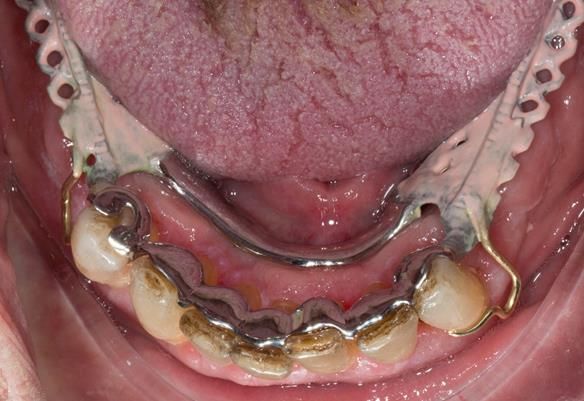

- Definitive dentures (Mk 2) – complete upper metal reinforced and lower cobalt chromium based partial of hygienic Scandinavian design to be made 9 - 12 months after extractions of all upper teeth and LR5 and LL4

The clinical situation and treatment process is shown in detail below with photographs.

The patient has been successfully rehabilitated and is now having periodontal maintenance from Syed Abad, Specialist in Periodontics at the practice. His quality of life has improved considerably. The clinical prosthodontics was provided by me and the technical work by Rowan.